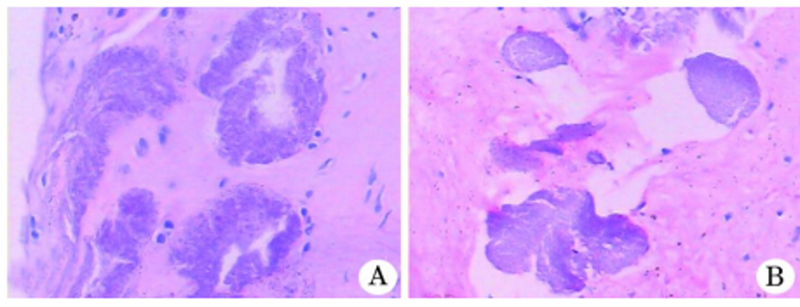

图4.膜组织内见多灶、团块状紫蓝色钙化结晶体沉积